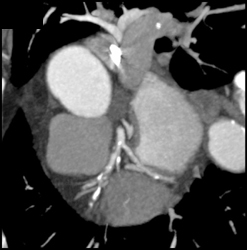

Diagnosis

Enlarged Lv